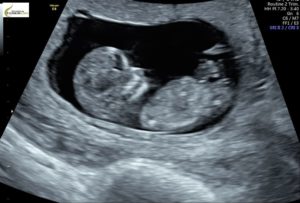

Ungarn: Gravide må lytte til barnets hjerteslag før de søker om abort

Fra og med idag må alle gravide kvinner i Ungarn som ønsker abort, høre på fosterets hjerterytme før de bestemmer seg for å abortere barnet eller ikke.